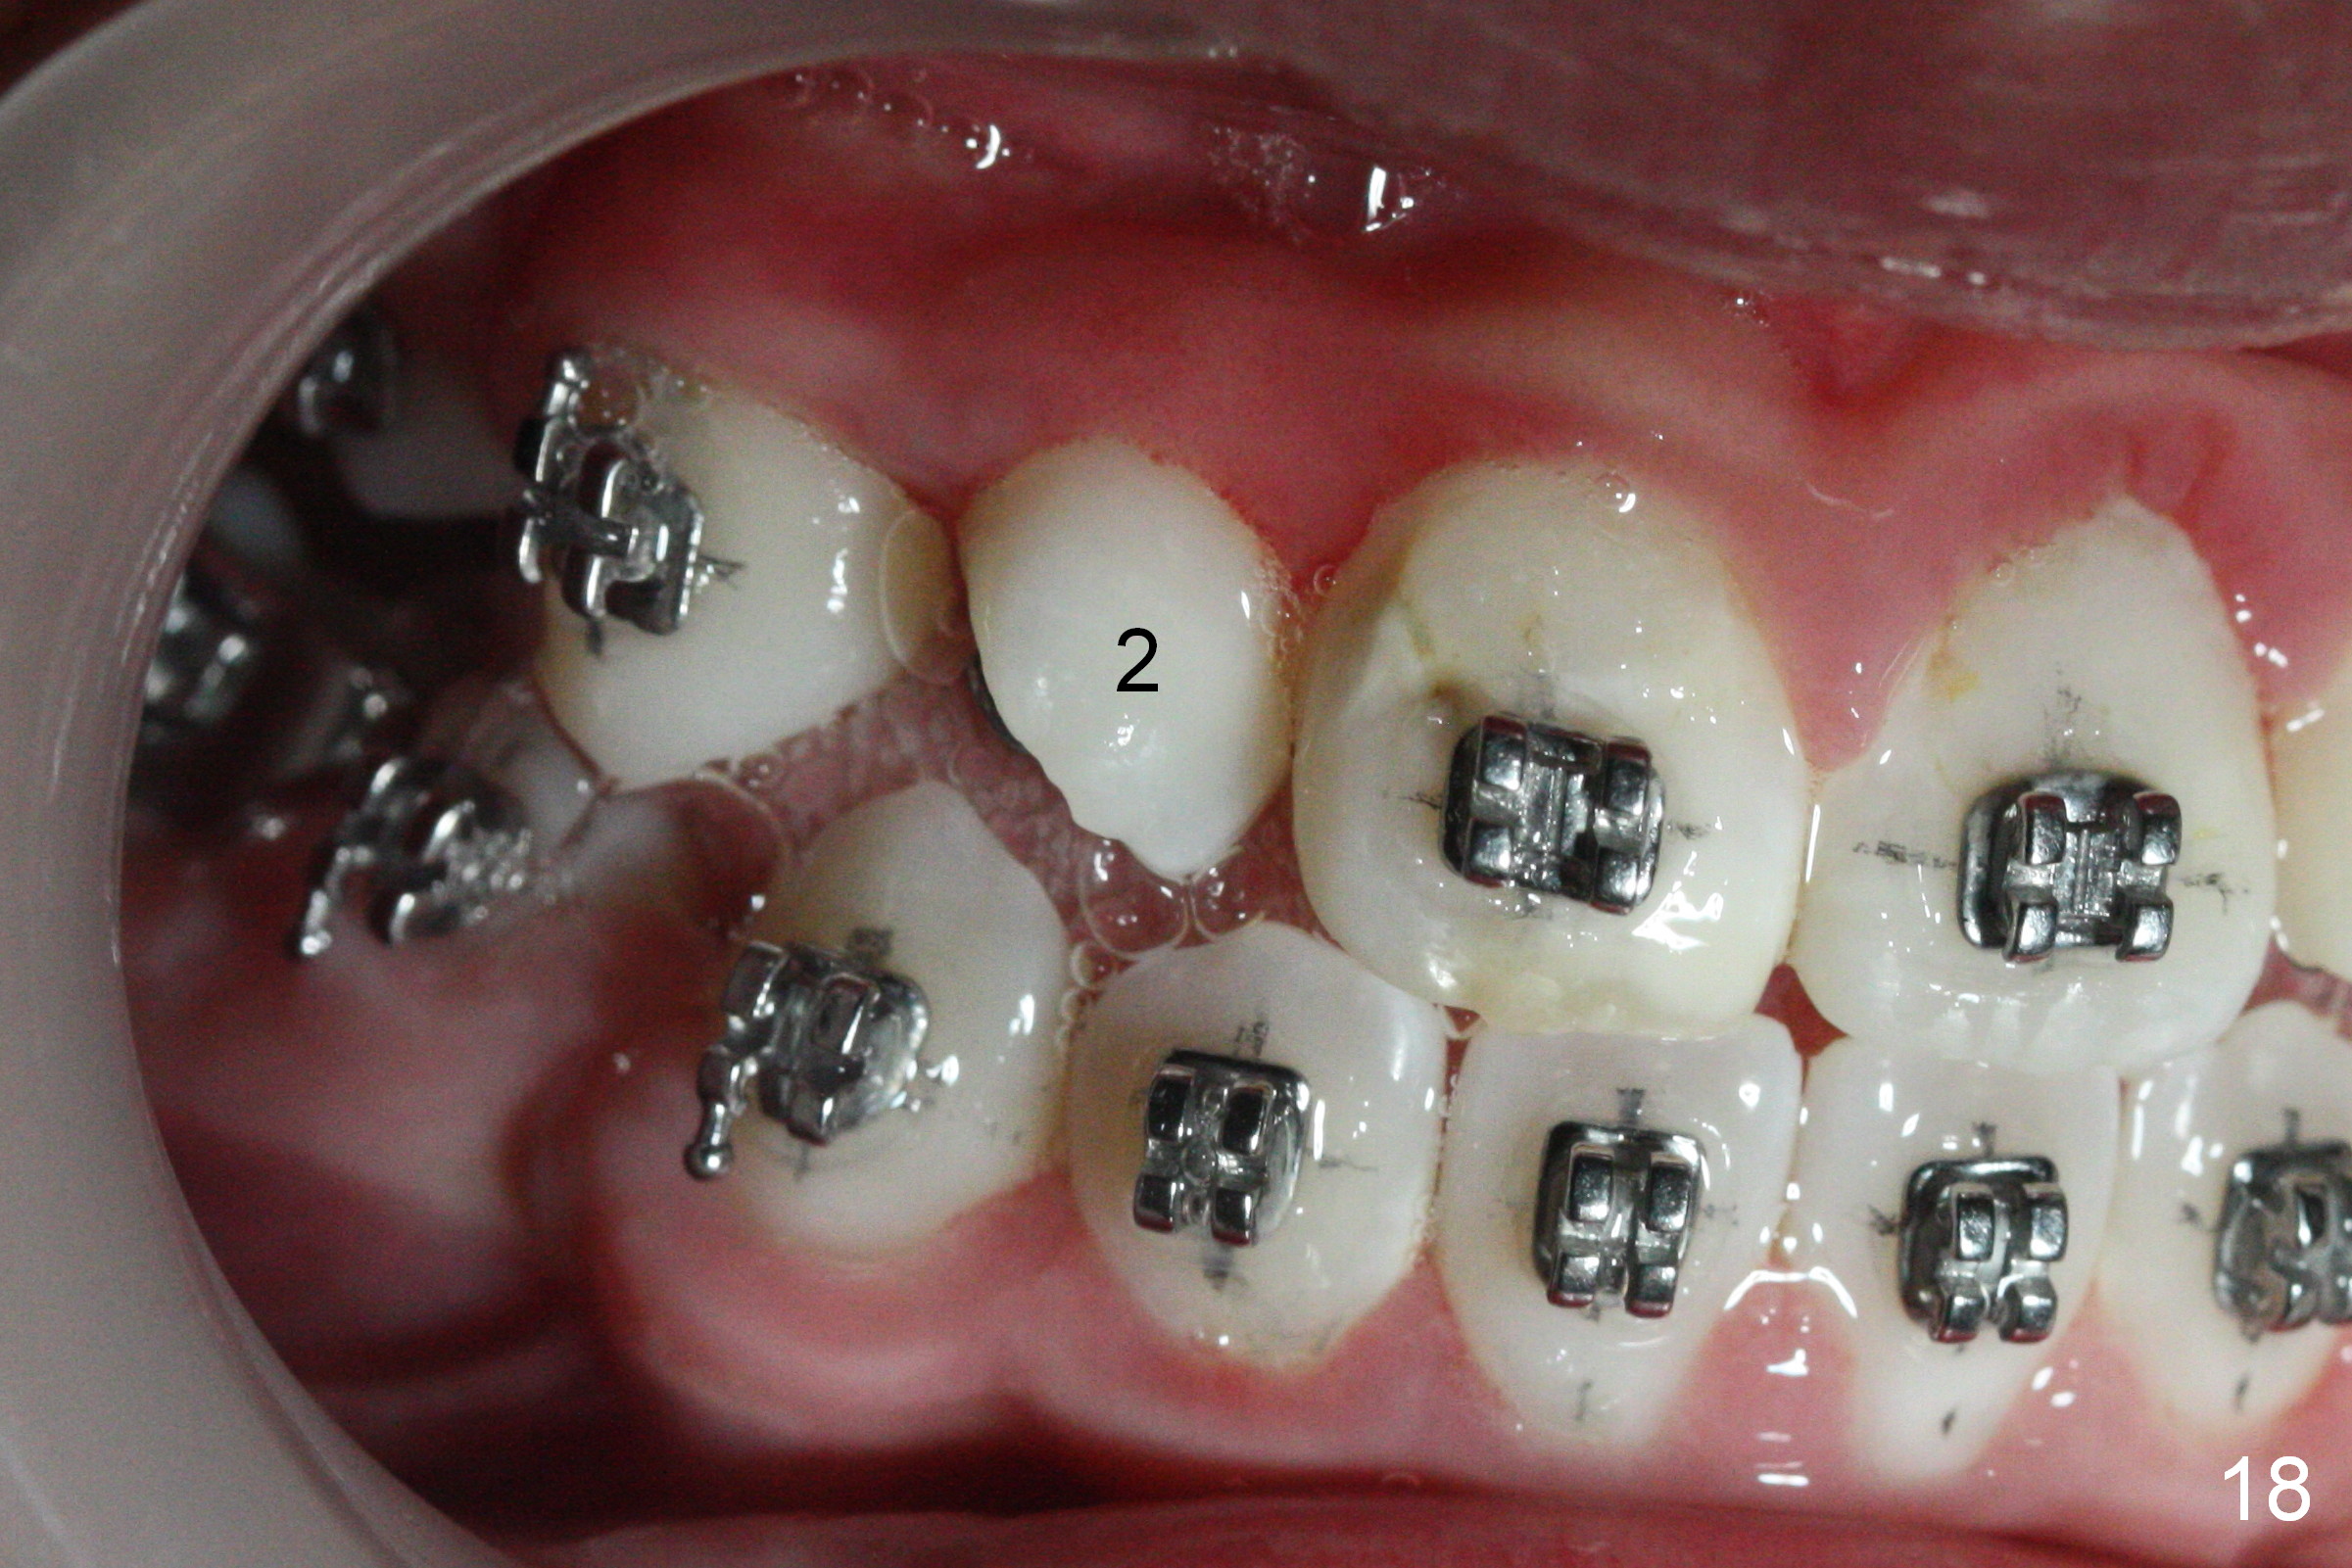

Three visits after open coil spring and 1 visit after sling shot, U2 cross bite is corrected (Fig.18,19). Due to UR2 rotation (Fig.19), bracket cannot be placed (Fig.20, 16 niti). Power chain x 3 is placed between UR2 and 3 to gain space for bracketing, which turns out not working. UL2 bracket is placed upside down for torque.